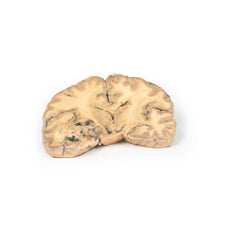

3D Printed Ruptured Berry Aneurism

Pathology

The specimen shows the basal surface of the brain. There is a saccular aneurism 5 mm in diameter at

the junction of the right internal carotid and the posterior communicating artery, which has ruptured. There is

subarachnoid blood in the immediate area in the cisterna magna and on the inferior surface of the right frontal

lobe. There is a similar unruptured aneurysm on the left side. The right frontal lobe appears softer and more

friable anteriorly